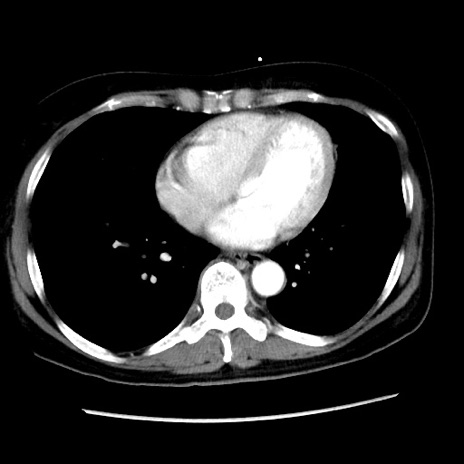

冠状断像

矢状断像